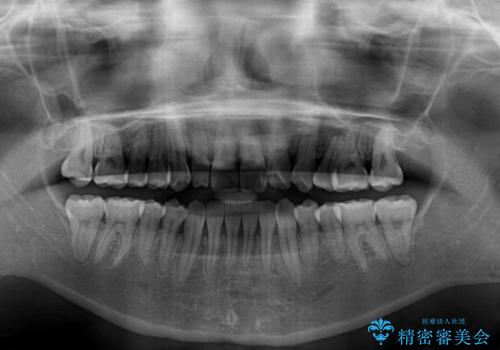

骨格的に下顎が右側に変位していたため、上下正中を合わせることは困難であることは分かっていました。それでも、なるべく合わせるようにとしたため、治療期間は長期間となりました。

長期間とはなりましたが、咬み合わせが改善され、患者様には大変満足していただきました。